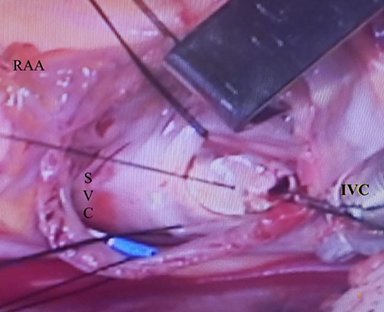

Cirugías reales

En esta sección se visualizarán cirugías reales en pacientes. Las fotografías por lo tanto

-si bien claras- en ocasiones privilegian la seguridad del paciente antes de

la exposición anatómica ideal.